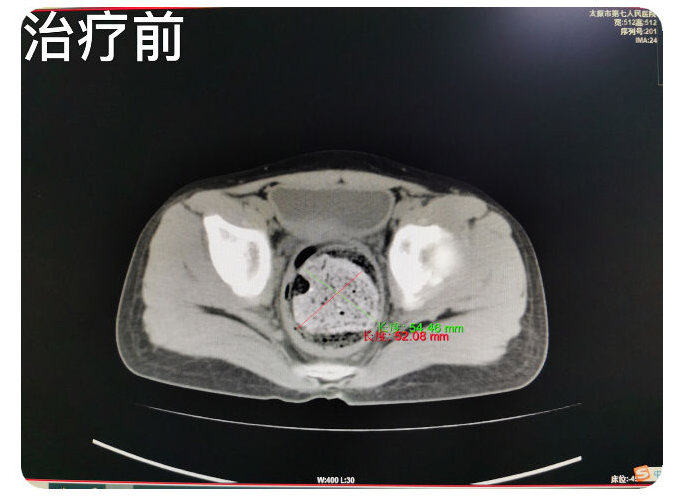

患儿九岁,主因排便控制不佳两月余,辗转就诊于省内多家医院,未明确诊断,治疗效果欠佳,肛门失禁症状逐渐加重,患儿及家属均承受了极大的心理及经济负担,后来患儿家属慕名就诊于成人快手 翟春宝主任医师门诊。翟主任通过仔细询问病史,细致查体后,考虑为粪性嵌塞引起的肛门失禁。入院检查CT,确认患儿直肠、乙状结肠高度扩张,内有高密度巨大粪块经过讨论为患儿制定了个体化的综合治疗方案。并就患儿的病情与家属充分沟通,缓解了患儿及家属的焦虑情绪,增强了患儿家属对治愈疾病的信心。经过10余天的规范化综合治疗,患者粪性嵌塞较前明显好转,仍有部分肠管扩张,肛门失禁症状得到治愈,无不适主诉,达到出院标准。